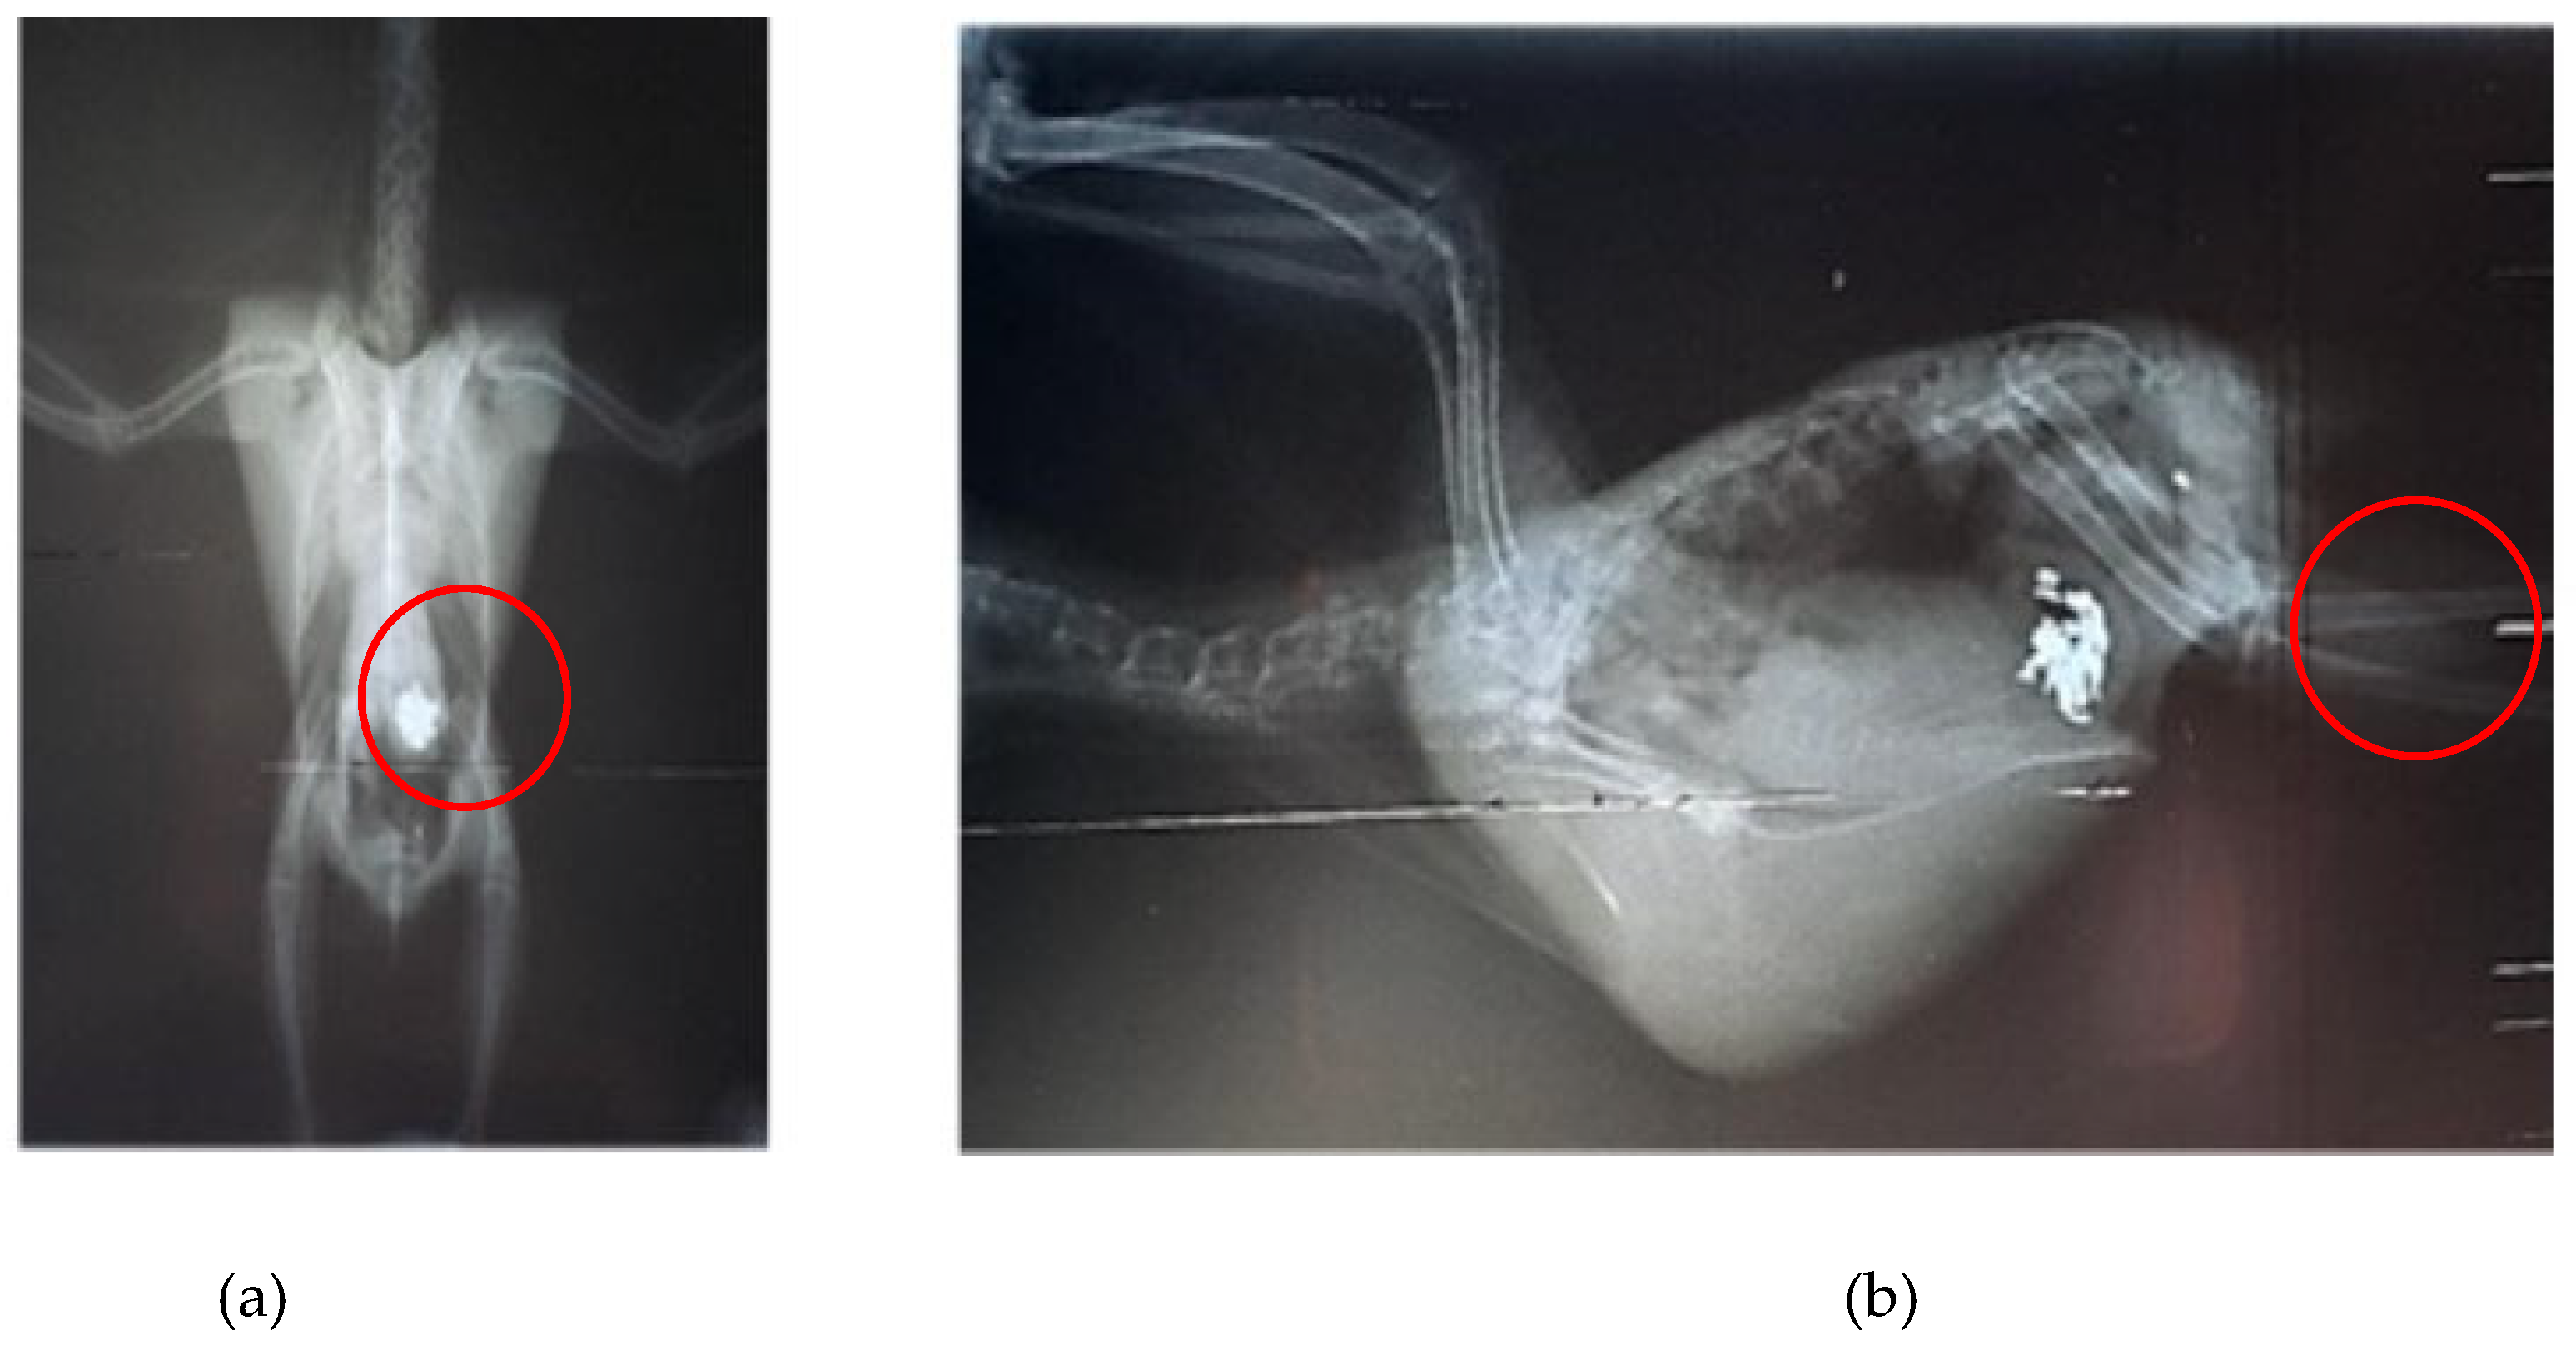

- Pinheiro, E.C.; Melo, R.C.; Grespan, A.; Peixoto, T.M.B.; dos Santos, M.H.; Cabral, L.A.R.; Costa, P.P.C. Heavy Metal Poisoning in a Cockatiel (Nymphicus hollandicus). Acta Sci. Vet. 2018, 46, 251. [CrossRef]

- Santos, C.B.; Canavessi, L.; Silva, A.H.; Telles, P.H.F.; Cubas, Z.S. Heavy metal poisoning in periquito (Brotogeris Chiriri): case report. Arch. Health Invest. 2021, 7, 11. [CrossRef]